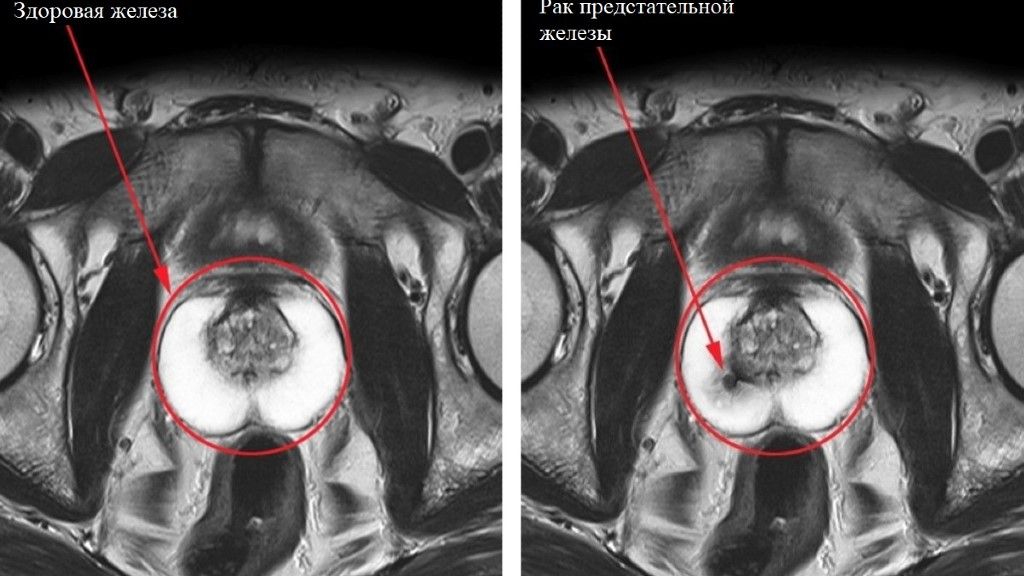

Мультипараметрическая магнитно-резонансная томография (мп МРТ) простаты занимает ведущее место в диагностике и лечение рака предстательной железы.

Сопоставление дооперационной «МРТ картинки» с результатами морфологического исследования после простатэктомии показало, что данная методика обладает прекрасной чувствительностью в выявлении и определении локализации Рака предстательной железы, особенно при размере очага более 10 мм.